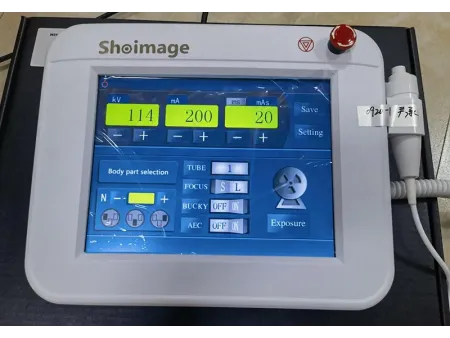

Integra una pantalla táctil de 7 pulgadas que permite gestionar de forma intuitiva las funciones del equipo, junto con un sistema avanzado de adquisición digital que proporciona imágenes nítidas, consistentes y de alta resolución, adaptándose a los requerimientos de diagnóstico más exigentes. Está disponible en dos modelos: SHO-DDX03 y SHO-DDX04, ambos con varias configuraciones de potencia para ajustarse a distintos flujos de trabajo: 20 kW / 200 mA, 20 kW / 320 mA, 32 kW / 400 mA, 40 kW / 500 mA, 50 kW / 630 mA. Para aplicaciones clínicas más complejas que requieren mayor capacidad, el modelo SHO-DDX04 alcanza una potencia de hasta 65 kW / 800 mA, garantizando imágenes de alta calidad incluso en estudios que demandan una penetración más profunda o un nivel superior de detalle.

| Cabezal principal | Panel de control con pantalla táctil de 9.7 pulgadas |

Equipado con una pantalla táctil LCD a color de 7 pulgadas, brinda una experiencia de uso rápida e intuitiva, facilitando cada paso del proceso.

Permite ajustar los parámetros de exposición de forma sencilla y precisa, facilitando una experiencia de uso cómoda y eficiente.

| Generador de rayos X | ||||

| Modelo | Serie SHO-DDX03 | |||

| Potencia de salida (kW) | 20 | 32 | 40 | 50 |

| Corriente (mA) | 10-320 | 10-400 | 10-500 | 10-630 |

| Voltaje (kV) | 40-125 | 40-125 | 40-125 | 40-150 |

| mAs (mAs) | 0.1-320 | 0.1-400 | 0.1-400 | 0.1-630 |

| Tiempo de exposición (s) | 0.00-6.3 | |||

| Tamaño del enfoque | 1.0/2.0 | 1.0/2.0 | 1.0/2.0 | 0.6/1.2 |